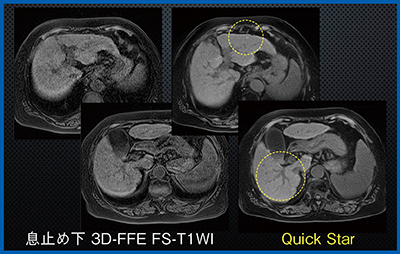

症例1は,肝細胞がん(HCC)治療後の経過観察の症例である。3D-FFE脂肪抑制T1強調画像では,息止め不良のため脈管構造や過形成結節が不明瞭であるが,Quick Starでは自由呼吸下でも肝実質が均一に描出されており,結節や脈管も明瞭である(図1)。また,別の症例では,後腹膜臓器の副腎や腎臓,膵臓などが3D-FFEよりもシャープかつ高コントラストに描出されていた。

図1 症例1:肝細胞がん(HCC)治療後の経過観察(70歳代,女性)